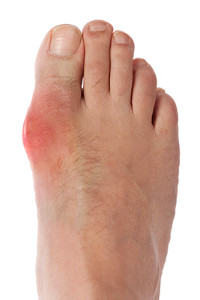

Everything You Need to Know About Gout

Gout, typically found in diabetic patients, is an unusually painful form of arthritis caused by elevated levels of uric acid in the bloodstream. The condition typically strikes the big joint on the big toe. It has also been known to strike the knees, elbows, fingers, ankles and wrists—generally anywhere that has a functioning, moving joint.

This form of arthritis, being particularly painful, is the leftover uric acid crystallizing in the blood stream. The crystallized uric acid then travels to the space between joints where they rub, causing friction when the patient moves. Symptoms include: pain, redness, swelling, and inflammation. Additional side effects may include fatigue and fever, although reports of these effects are very rare. Some patients have reported that pain may intensify when the temperature drops, such as when you sleep.

Causes of Gout

If inflammation is experienced, often resulting in severe pain located in the foot, you may have a condition referred to as gout. This condition is caused by a large amount of uric acid in the blood, which is a waste product secreted by the kidneys. Crystals are formed by excessive uric acid which adheres to the joints, causing severe inflammation. There are many causes of gout, including predisposed inherited genes, kidney disease, obesity, diet, and high blood pressure. If a healthy lifestyle is practiced, which includes limiting alcohol and avoiding foods that cause elevated uric acid levels, the attacks may be controlled. Please consider scheduling a consultation with a podiatrist for more information about gout.

What Is Gout?

Gout is a type of arthritis caused by a buildup of uric acid in the bloodstream. It often develops in the foot, especially the big toe area, although it can manifest in other parts of the body as well. Gout can make walking and standing very painful and is especially common in diabetics and the obese.

Gout can easily be identified by redness and inflammation of the big toe and the surrounding areas of the foot. Other symptoms include extreme fatigue, joint pain, and running high fevers. Sometimes corticosteroid drugs can be prescribed to treat gout, but the best way to combat this disease is to get more exercise and eat a better diet.